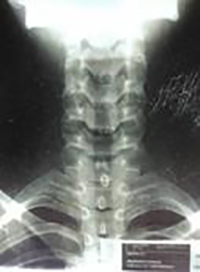

Se indica realizar resonancia magnética, evidenciando la existencia de una lesión ocupante de espacio a nivel de C5-C6, de aspecto subdural. En vista de estos hallazgos, se procede a realizar laminectomía en C5-C6 con abordaje posterior en donde, posterior a incisión de la duramadre, se aprecia la existencia de una lesión quística. Se logra realizar exéresis completa de la misma, ya que no presenta adherencias a la médula espinal. La laminectomía se puede apreciar en la radiografía de la columna cervical postoperatoria (Figura 1).

Figura 1: Radiografía de columna cervical anteroposterior, donde se evidencia laminectomía en C5-C6 con abordaje posterior.

Si bien es cierto que, en los controles médicos posteriores, la paciente demuestra mejoría significativa de los síntomas neurológicos antes descritos, al año de la cirugía se le indica realizar nuevamente una resonancia magnética, en vista de presentar molestias a nivel cervical. En el estudio, se aprecia una pérdida de la lordosis cervical, por lo cual se le realiza fijación de la columna vertebral con corpectomía cervical a nivel de C5, insertándose malla y placa de titanio, logrando la estabilidad de la columna y mejoría de la cervicalgia (Figura 3).

Figura 3: Radiografía lateral de columna cervical, donde se evidencia fijación de la columna, mediante abordaje anterior, con colocación de malla y placa de titanio, por técnica de corpectomía cervical a nivel de C5.